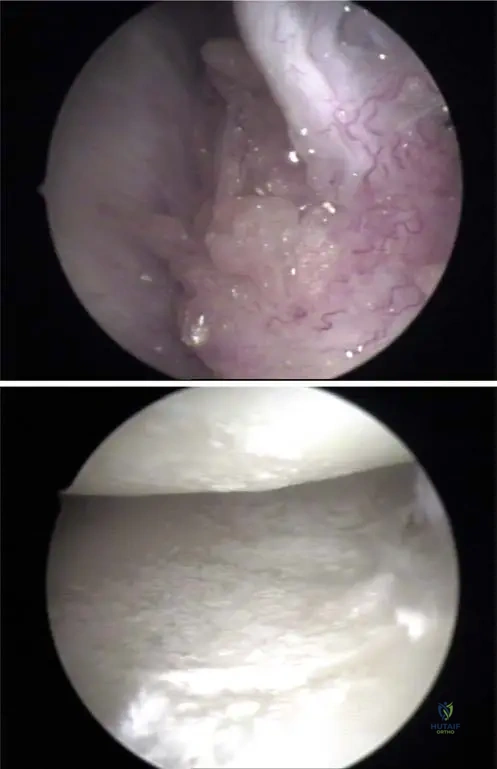

A 62-year-old male undergoes arthroscopy for chronic knee pain and suspected inflammatory arthritis. During the procedure, white, chalky deposits are noted within the joint.

Correct Answer: C

Rationale: The clinical context for Fig. 7.5 a, b states, "Deposits of urate crystals may occur in the synovium (a) and in the cartilage of the knee joint (b) as visualized by arthroscopy." This indicates that both these tissues are common sites for urate crystal deposition within the joint. While menisci are cartilaginous structures, the description is more encompassing of the joint's cartilage and synovium.

A 50-year-old male undergoes arthroscopy for chronic knee pain and suspected gout. During the procedure, the surgeon observes white, chalky deposits within the joint. According to the provided information, where might these urate crystals be found within the knee joint during arthroscopy?

Rationale: The clinical context for Fig. 7.5 a states, "Deposits of urate crystals may occur in the synovium (a) and in the cartilage of the knee joint (b) as visualized by arthroscopy." Therefore, finding crystals within the synovium is a correct arthroscopic observation. While they can also be in cartilage, "only" options are often incorrect, and synovium is a distinct location mentioned.

Question 43

During an arthroscopic examination of a 60-year-old male's knee, the surgeon notes glistening white deposits on the joint surfaces. These deposits are consistent with urate crystals. Based on the provided images and context, where else within the knee joint might these urate crystals be visualized arthroscopically?

View Answer & Explanation

Correct Answer: B

Rationale: The clinical context for Fig. 7.5 b states, "Deposits of urate crystals may occur in the synovium (a) and in the cartilage of the knee joint (b) as visualized by arthroscopy." Therefore, finding crystals on the articular cartilage is a correct arthroscopic observation. The other options are not mentioned as specific arthroscopic locations for urate crystal deposits in the provided text.